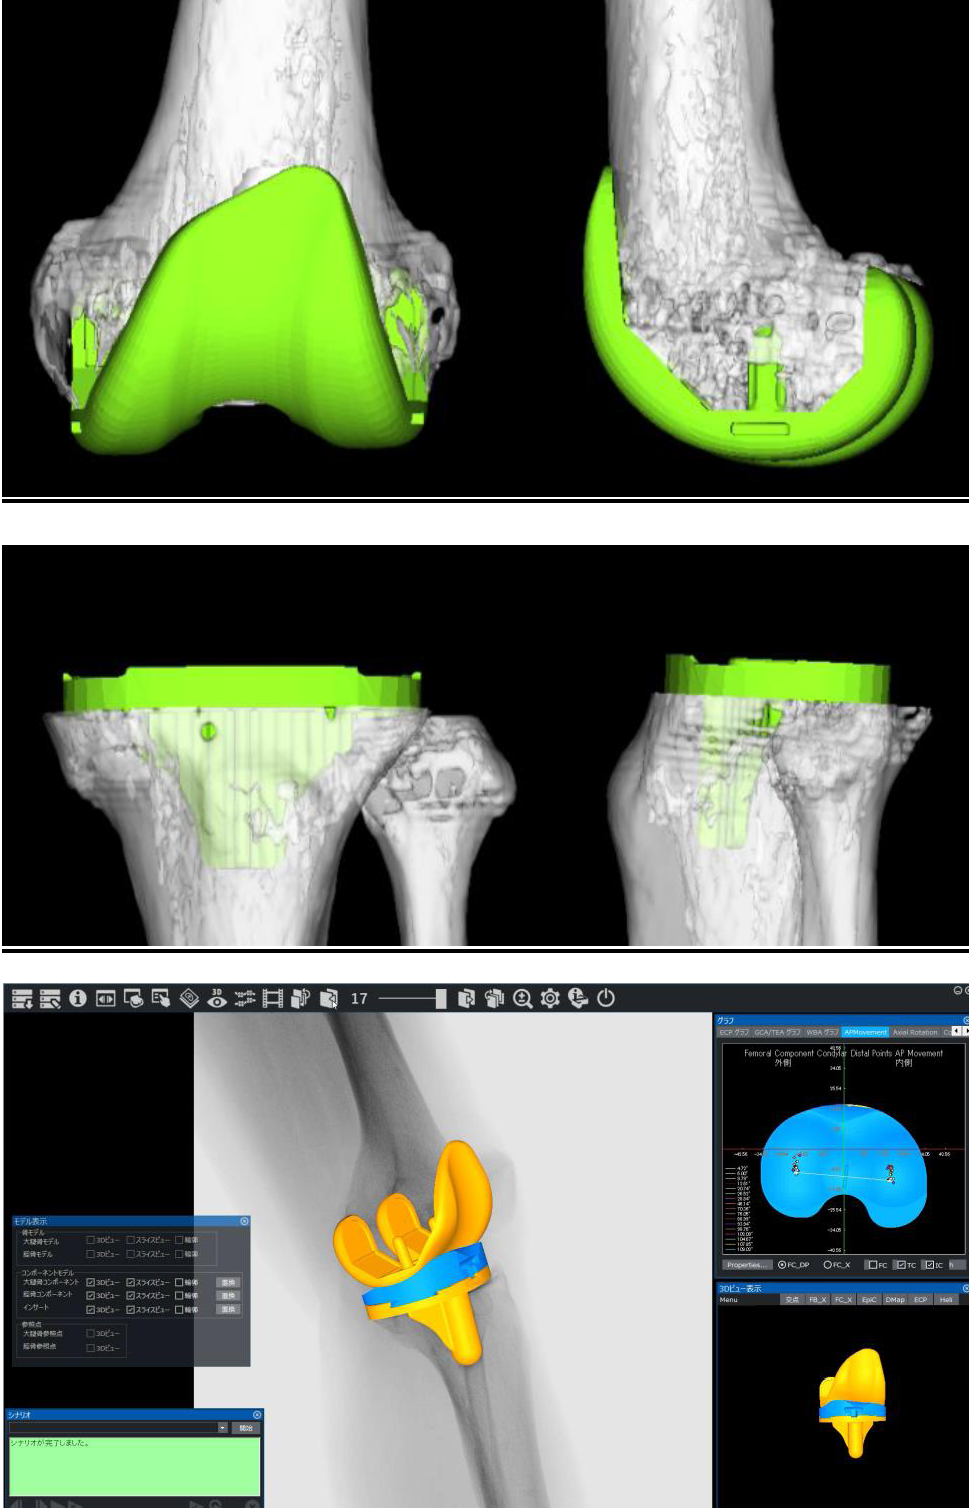

人工膝関節全置換術における3Dテンプレート・動作解析

当院では3次元術前計画ソフトウェア(LEXI社 Zedknee)を用いて患者様のCT画像から最適なインプラントの種類やサイズを手術前から把握することが出来るためより正確な手術が可能となりました。また、膝関節の動態解析が可能ですので術後の状態をより詳細に把握し、リハビリに還元することが可能です。